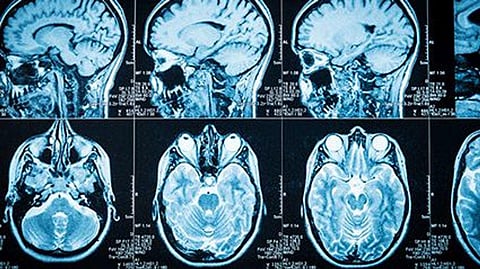

They compared brain connectivity -- various brain regions acting together in generating thought, emotion and behavior -- in 109 patients with serious depression to that in a control group of 55 volunteers without depression. MRI scans were used to identify which brain areas were communicating with others before and after treatment.

The researchers then rescanned participants' brains, counting the number of connections. They also retested for depression.